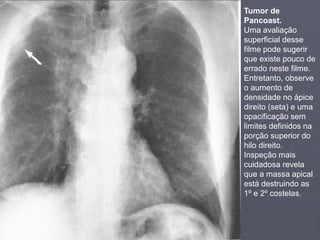

Tumor de Pancoast

► Antes de liberar um Rx como normal:

1. Observe atentamente os ápices de ambos os pulmões:

1. Este é um lugar comum para patologias pulmonares, como tumor

de Pancoast ou fibrose crônica.

2. Lesões neste localmente podem passar facilmente despercebidas

devido estarem escondidas pelas costelas e clavículas.

4. Observe o hilo:

1. Mudanças na forma ou densidade do hilo

podem passar facilmente despercebidas

5. Obtenha um filme em projeção lateral:

1. As mesmas anormalidades de um filme em PA

pode ser óbvias em um filme em perfil.

Tumor de

Pancoast.

Uma avaliação

superficial desse

filme pode sugerir

que existe pouco de

errado neste filme.

Entretanto, observe

o aumento de

densidade no ápice

direito (seta) e uma

opacificação sem

limites definidos na

porção superior do

hilo direito.

Inspeção mais

cuidadosa revela

que a massa apical

está destruindo as

1º e 2º costelas.